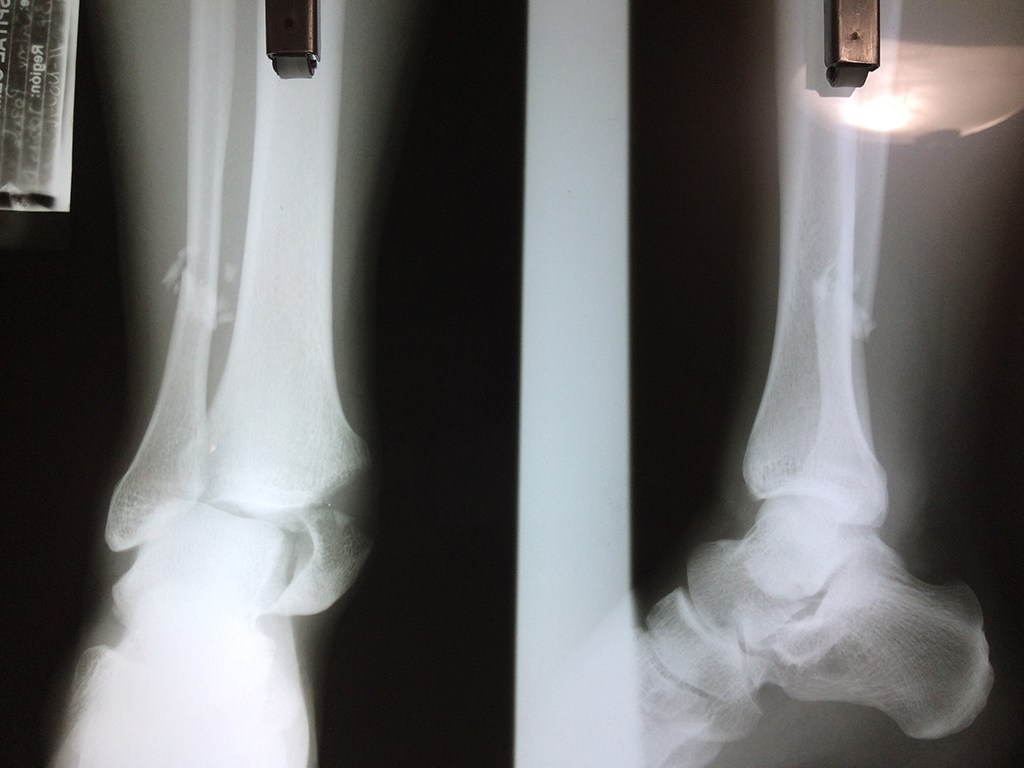

Cirugía de Tibia y Peroné

Una fractura de tobillo es la rotura de uno o más de los huesos del tobillo. Estas fracturas pueden ser:

Algunas fracturas de tobillo pueden requerir cirugía si:

Cuando se necesita cirugía, es probable que esta implique el uso de clavijas de metal, tornillos o placas para sostener los huesos en su lugar mientras la fractura se consolida. Los elementos de soporte pueden ser temporales o permanentes.